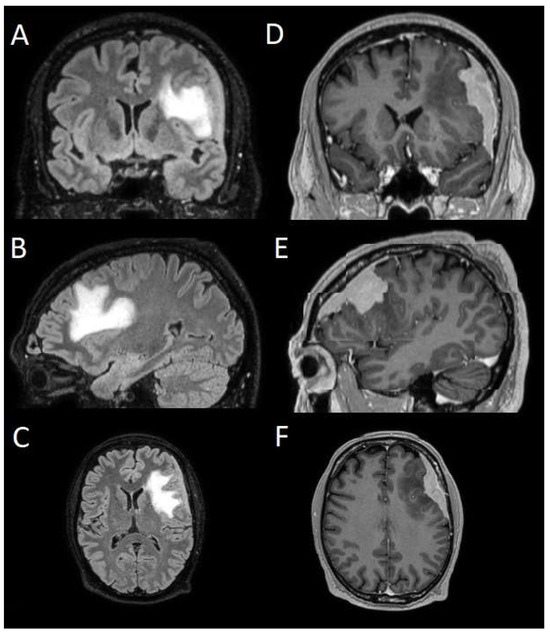

The patients underwent magnetic resonance imaging (MRI) at our center using a 1.5T or 3T Tesla MRI machine (Ingenia 3T, Philips Medical Systems, Best, The Netherlands) with the standard oncological protocol [14]. Specifically for analysis, the sequences collected were T1-weighted with contrast enhancement to estimate tumor volume and conformation and FLAIR (fluid-attenuated inversion recovery) to quantify PE (Figure 1). We manage the preoperative imaging in a DICOM (digital imaging and communications in medicine) format. The images from the T1-weighted sequences with contrast enhancement and FLAIR sequences in the DICOM format were processed through the Slicer website [15]. Tumor and PE segmentation was performed using a voxel-based analysis that integrated automated and manual methods (Figure 2).

Figure 1. Sequences selected for the segmentation. (AC) Coronal, sagittal, and axial FLAIR sequences to quantify PE. (DF) Coronal, sagittal, and axial T1-weighted sequences with contrast enhancement to estimate meningioma volume. FLAIR: fluid-attenuated inversion recovery; PE: peritumoral edema.